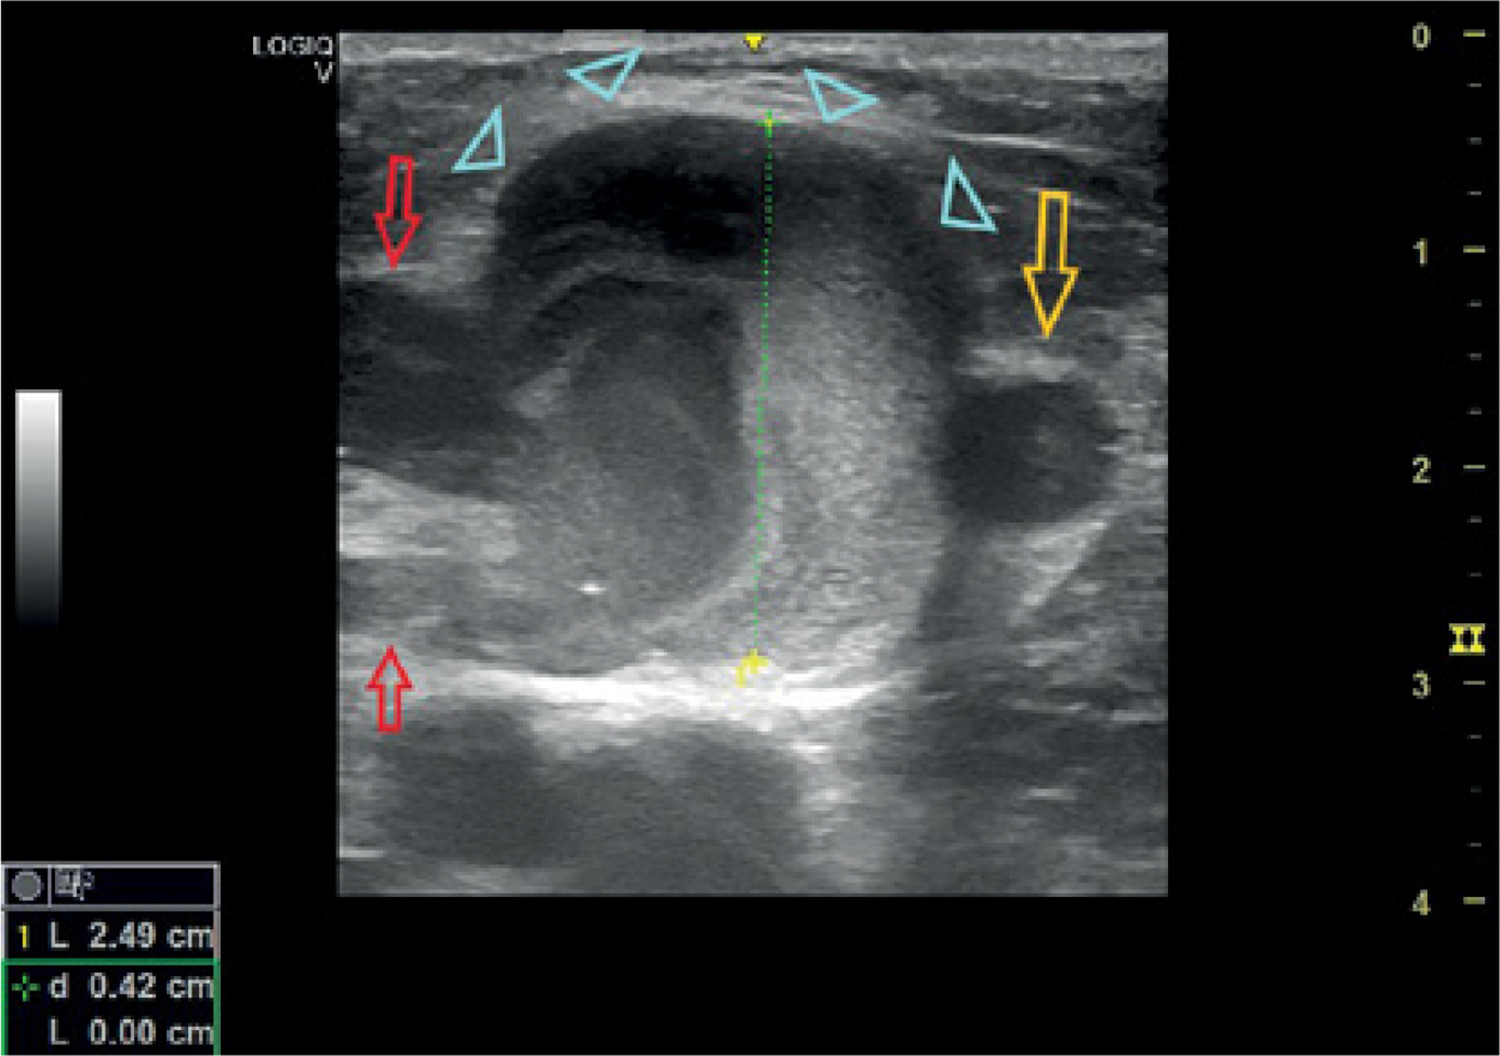

Figure 7

A 50-year-old man presented with a palpable venous aneurysm (2.5 cm in diameter) near the saphenofemoral junction (at about 1 cm distally). He complained about periodical mild pain. He had abdominal surgery for trauma 7 years previously, but no trauma in the inguinal area was reported (orange arrow: great saphenous vein, light blue arrowheads: venous aneurysm, red arrows: draining veins to the anterior accessory saphenous branch) (Supplementary material)

Endovenous laser (EVLA) or radiofrequency ablation (RFA) is an alternative treatment option for superficial VAs with large feeding veins [49, 63, 87]. This is especially true in VAs located in the route of great and small saphenous veins or in their accessory branches [90]. Ablation has a low rate of recanalization and reflux (higher with RF compared to EVLA) [91]. This may be a result of the thickening of the venous wall due to chronic inflammation [68]. They are contraindicated in larger lesions (above 2.5–3 cm) as failure rates are increased [14, 34, 68, 91, 92]. Rare complications include damage to the adjacent skin or neuromuscular structures, as well as endothelial heat-induced thrombosis (EHIT) leading to deep venous thrombosis (DVT) and PE [38, 91]. For superficial VAs close to the saphenofemoral or saphenopopliteal junction, safe ablation can be performed only if lesions are > 3 cm from the junction. If the distance is < 3 cm, ablation should be performed only after open excision and high saphenous ligation (Figure 7) [10].

Two additional images from patients who presented in our clinic upon completion of this review are included (Figures 6 and 7). Although not analyzed extensively, they provide further insight and offer further illustrative value.